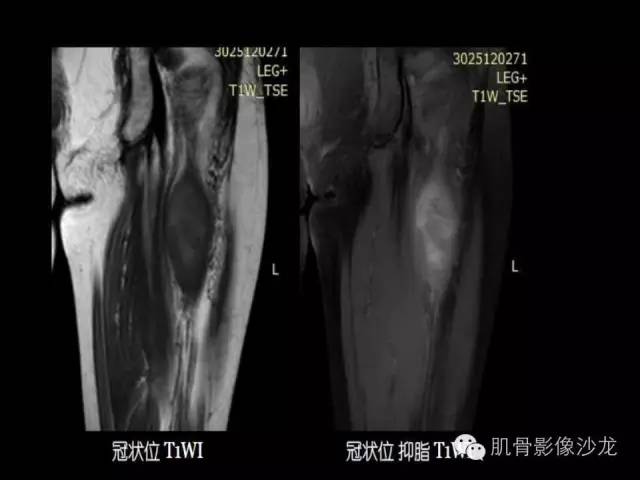

【病例】恶性外周神经鞘膜瘤1例MR影像表现